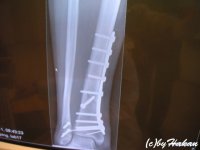

Såhär kan det gå när man åker på deras kryssningar :arsele

inget jag rekommenderar dock

Bifogat

• spikar.jpg

spikar.jpg

21.6 KB · Visningar: 89